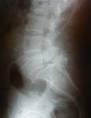

Ocurre generalmente después de los 50 años y es más frecuente en mujeres, el espacio más afectado es L4-L5. Es un problema degenerativo de los ligamentos que fijan la columna, los cuales se vuelven laxos, permitiendo el deslizamiento del cuerpo vertebral, con subluxación y erosión de las facetas articulares, ocasionando dolor lumbar o lumbo-ciático. La posición erguida y la forma de caminar parecen contribuir al desarrollo de este problemas. Existen factores hereditarios que predisponen a algunos sujetos a desarrollarla. El tratamiento inicial no quirúrgico, incluye fármacos antiinflamatorios no esteroideos, modificación de actividades deportivas , inmovilización con ortesis y fisioterapia. El tratamiento Quirurgico es una artrodesis sólida, con tornillos pediculares.